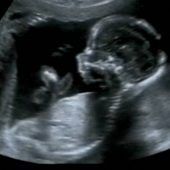

Ein gesundes Kind – nichts wünschen sich werdende Eltern mehr. Doch wie lässt sich schon vor der Geburt erkennen, ob es dem Baby gut geht? Antworten soll die „Pränataldiagnostik“ liefern. Was leistet sie? Und: Wo sind die Grenzen? Fakten anlässlich... zum Artikel

Ultraschall-Untersuchungen liefern nicht nur wichtige Hinweise auf die Schwangerschaftswoche oder die Lage des Kindes. Damit lässt sich auch das Risiko für Trisomie 21, also das Down-Syndrom, abschätzen. Dazu misst der Arzt auf dem Ultraschallbild... zum Artikel